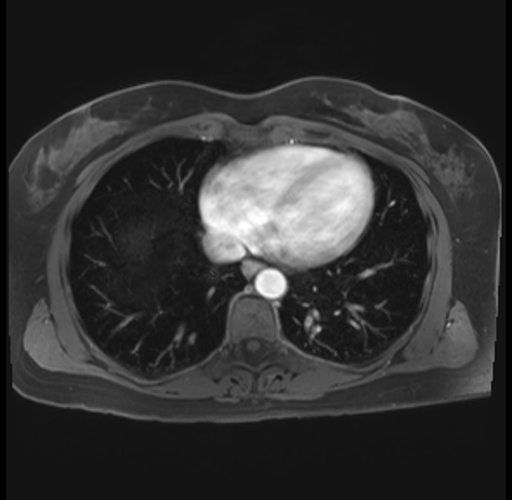

Imaging Analysis

Look through the patient's CT scan to identify any areas of concern for the necessary procedure.

Based on your CT findings, which issue(s) are present and would give reason for "planned slowing down moment(s)" in this case?

Considering a standard distal pancreatectomy procedure, what step(s) of the operation would you do differently in this case?